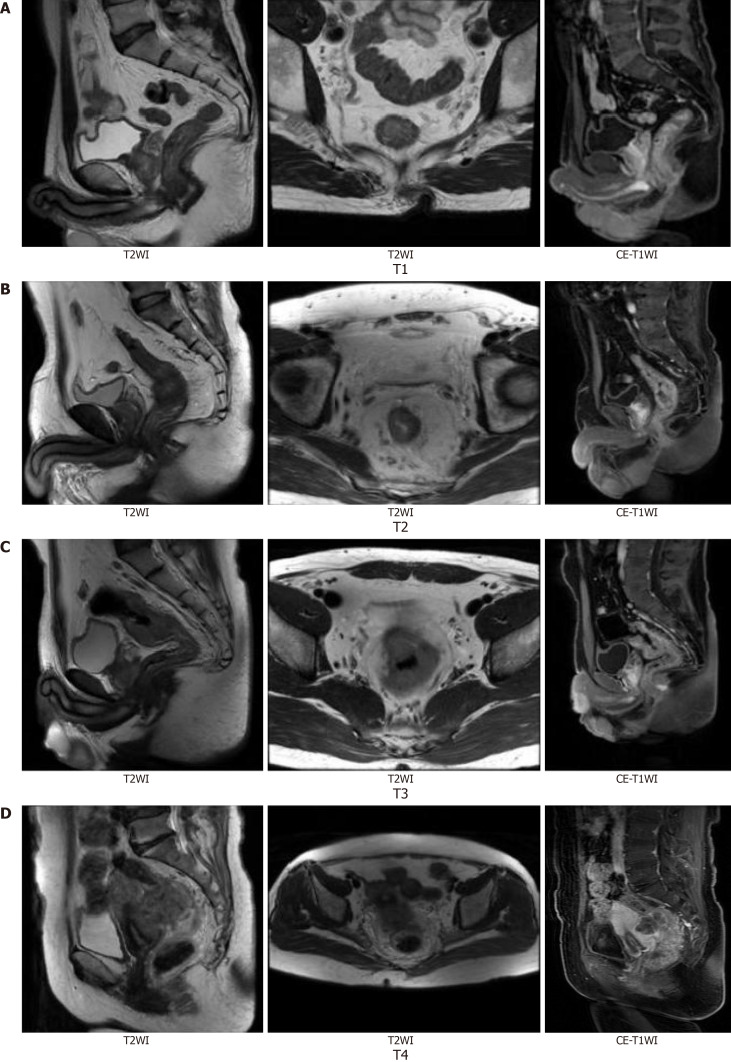

Methods: Eighty patients (age: 42-78 years) diagnosed with primary rectal cancer were enrolled. Baseline MRI examinations were performed to evaluate tumor size, T stage, circumferential resection margin status, extramural vascular invasion (EMVI), and lymph node metastasis. Serum CEA levels were concurrently measured. Statistical methods were used to analyze correlations.

Results: Tumor size, T stage, EMVI, and lymph node metastasis were significantly correlated with serum CEA levels (P < 0.05). Multivariate analysis identified T stage and lymph node metastasis as independent factors influencing serum CEA levels.